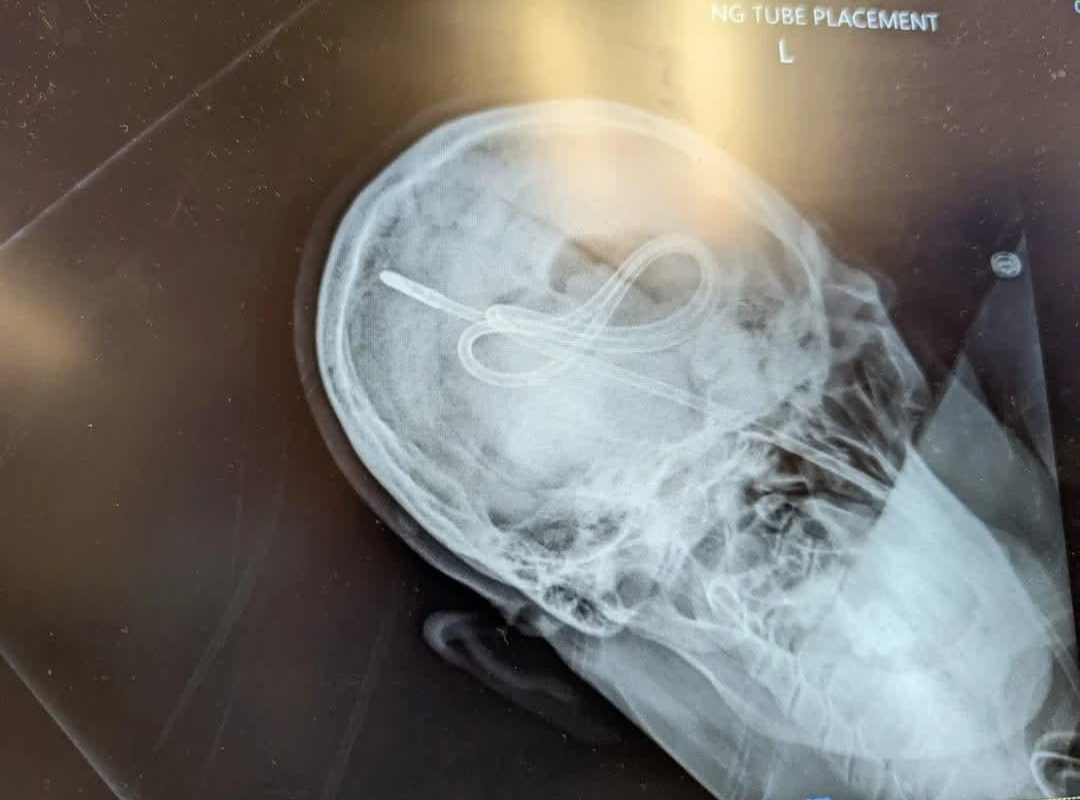

PMCT Images. Nurse advanced NG tube until she heard a pop, then tried an air bolus to ensure placement. Patient did not survive.

The Case: NG Tube Misplacement and Fatal Air Bolus

In a tragic incident, a nurse advanced an NG tube into a critically ill patient until hearing an audible “pop.” Believing the sound indicated gastric placement, she administered an air bolus (a common test to confirm tube position via auscultation of whooshing sounds). Shortly after, the patient deteriorated and died.

PMCT imaging later revealed devastating findings:

- Tracheobronchial Perforation: The “pop” signaled unintended tube entry into the trachea or bronchi, causing airway trauma.

- Pneumothorax: The air bolus introduced near the lungs led to a collapsed lung.

- Subcutaneous Emphysema: Air leakage into soft tissues further compromised respiration.

These complications confirmed that auscultation and air bolus tests alone are unreliable for verifying NG tube position.

PMCT imaging provided irrefutable evidence in this case, offering:

- Precise Localization: The tube’s path through the trachea into the pleural cavity was visualized.

- Identification of Secondary Injuries: Air emboli, lung collapse, and soft tissue damage were clearly mapped.

- Forensic Accountability: The images highlighted systemic flaws in procedural protocols.

Without PMCT, the exact mechanism of death might have remained speculative.